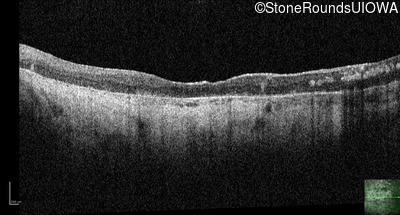

Optical Coherence Tomography - Left - Light Perception

Exemplar / OCT Stack